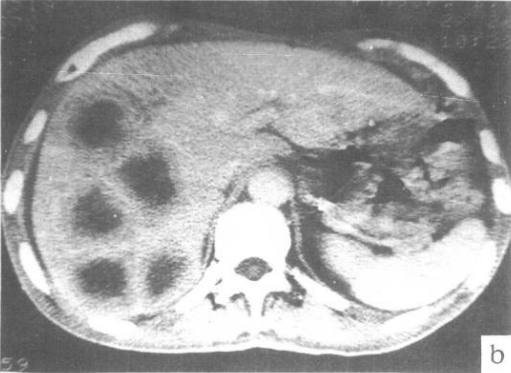

肝转移瘤

图片尺寸394x320